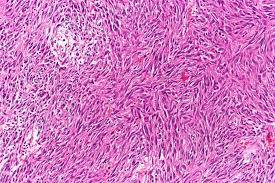

3. Gastrointestinal stromal tumor, GIST

• 위장관에서 발생하는 가장 흔한 mesenchymal 종양

2) 조직학적 소견

• 단일, 주변 조직과의 경계가 뚜렷한 종괴

• 대개 점막하층 또는 근육층에서 발생

• 세포 형태:

- spindle cell type: 가장 흔함

- epitheliod type도 존재

- 핵 다형성은 일반적으로 드묾

Gastrointestinal stromal tumor, Wikimedia Commons